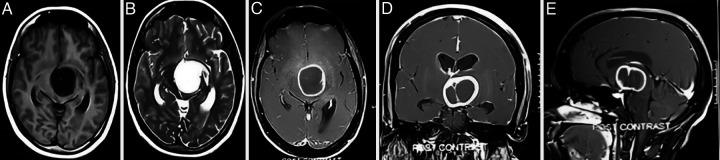

A 32-year-old female presented with progressive right-sided hemiparesis over several days. Magnetic resonance imaging revealed a cystic ring-enhancing thalamic lesion extending into the third ventricle. While supine, the patient underwent surgery via a right pericoronal parasagittal craniotomy followed by a contralateral interhemispheric transcallosal transchoroidal approach.

一名32岁女性在数天内出现进行性右侧偏瘫。磁共振成像显示一个囊性环形强化的丘脑病变延伸至第三脑室。患者仰卧位时,通过右侧冠状旁矢状开颅术,随后采用对侧半球间经胼胝体经脉络膜入路进行手术。